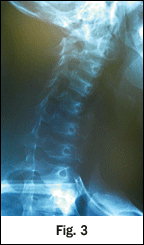

On the first spinal manipulation, he experienced a sudden increase in cervical tone of the left SCM, and reported a sudden decrease in pain with motion. No new pain with radiation into or down his left arm or with numbness in his fingers developed, nor did he develop any weakness in his left hand. He was seen subsequently for 12 conservative measures; 50 percent of the time he received spinal adjustments and he did improve. There was an indication of a relative contraindication to CSMT based upon the disease process. He previously had undergone radiological imaging, which revealed an antalgic list (Fig. 1), sigmoid-type curve and loss in cervical lordosis and a slight segmental flexion and anteriolisthesis (Fig. 2), consistent to a whiplash or CAD injury presentation. Cervical oblique (Fig. 3-4) failed to demonstrate any cervical stenosis. Open-mouth odontoid or dens (Fig. 5) failed to demonstrate any developmental deficiencies of the cervical spine, i.e., agenesis or odontoid hypoplasia. A low-force technique mode was chosen and discussed with the family. At the conclusion of care, the patient had experienced a complete recovery of his acute pain state.